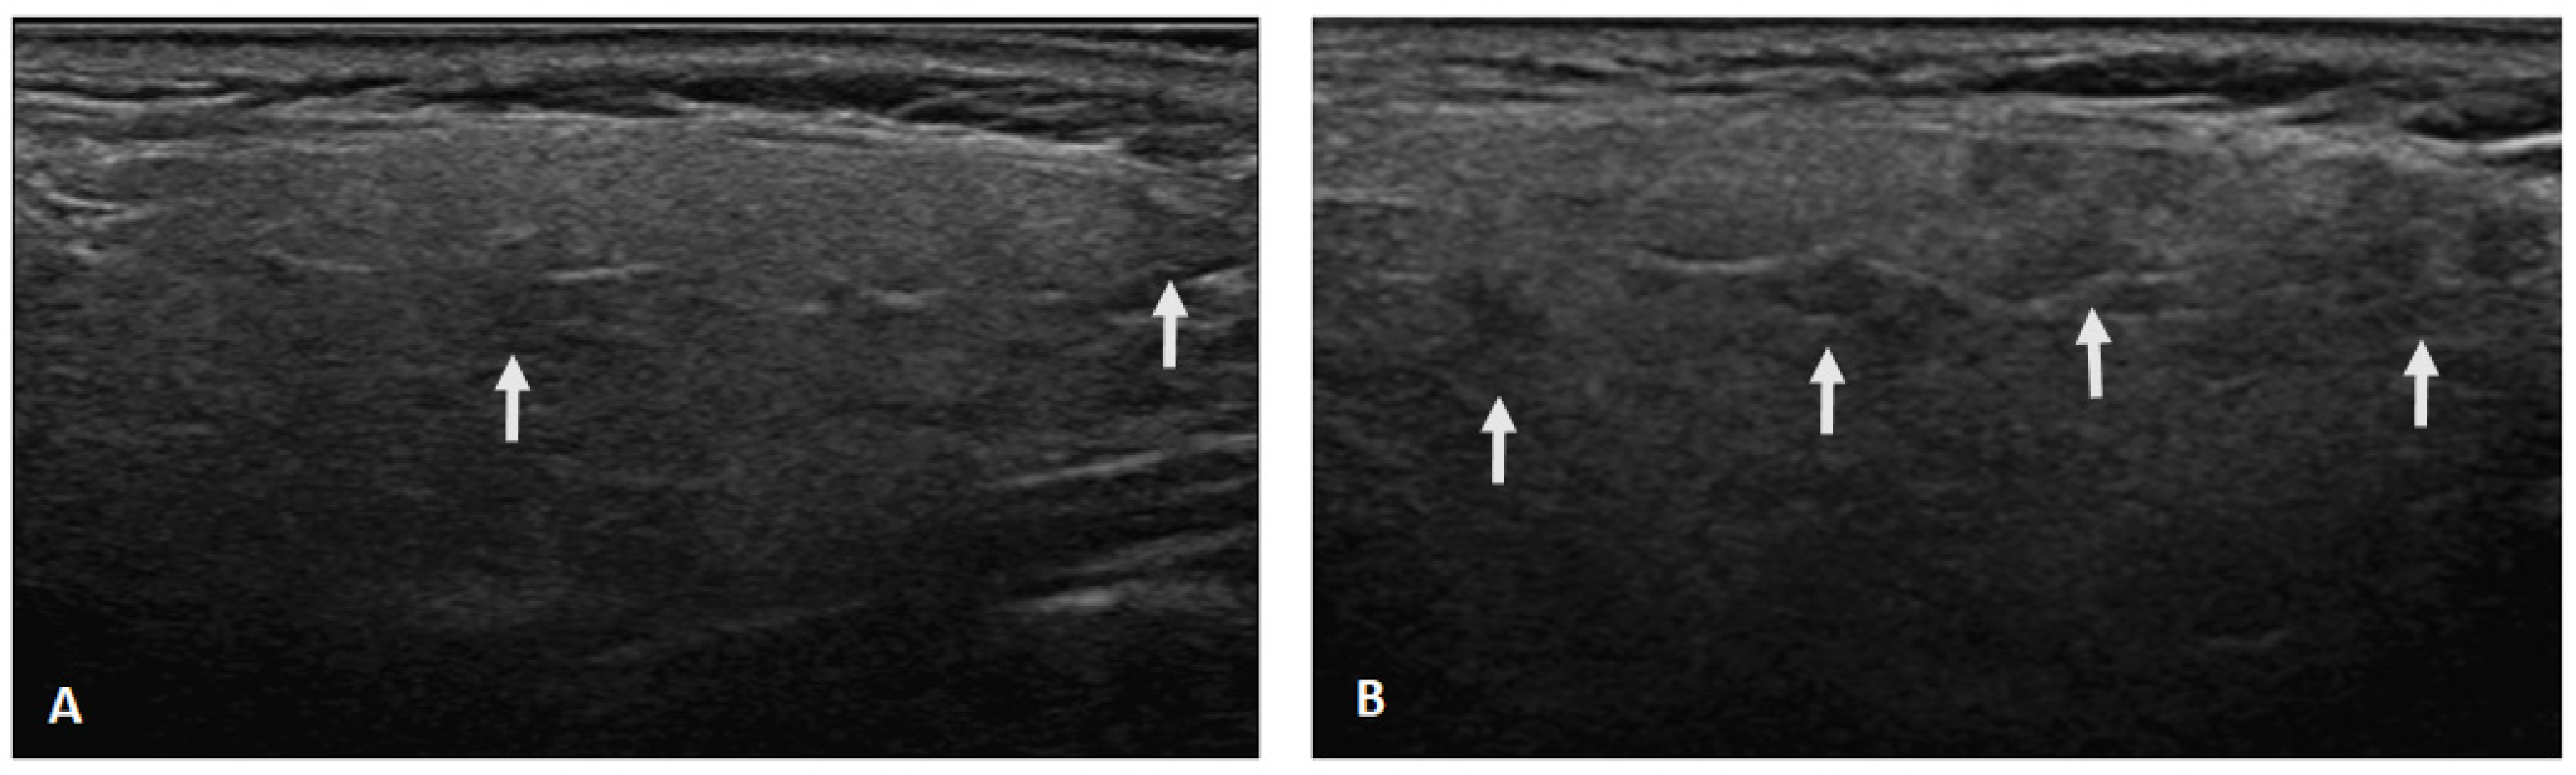

2.2. Salivary Gland Ultrasonography Examination